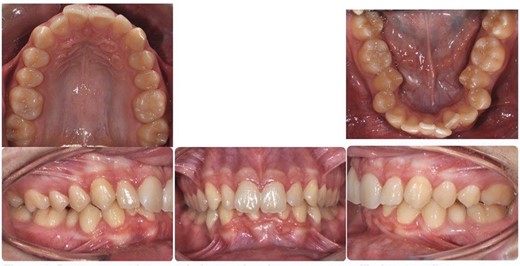

A 15-year-old male patient of Asian origin presented for orthodontic treatment with the chief complaint of crowding in his lower front teeth. Intra-oral clinical examination revealed severe crowding in the mandible, mild crowding in the maxilla, a bilateral class II canine relationship, retroclined upper incisors, impinging deep overbite and overjet of 5 mm (Fig. 1). His convex soft tissue profile and smile analysis revealed a decreased incisal show (Fig. 2).

Pretreatment intra-oral photos showing severe mandibular crowding.